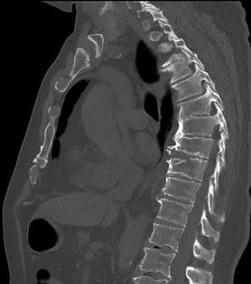

A 35-year-old male falls from a ladder and sustains localized thoracolumbar pain. He is neurologically intact. CT and MRI confirm an L1 burst fracture with 15 degrees of kyphosis, 30% canal compromise, and an intact posterior ligamentous complex.

Based on the Thoracolumbar Injury Classification and Severity (TLICS) score, what is the most appropriate management?